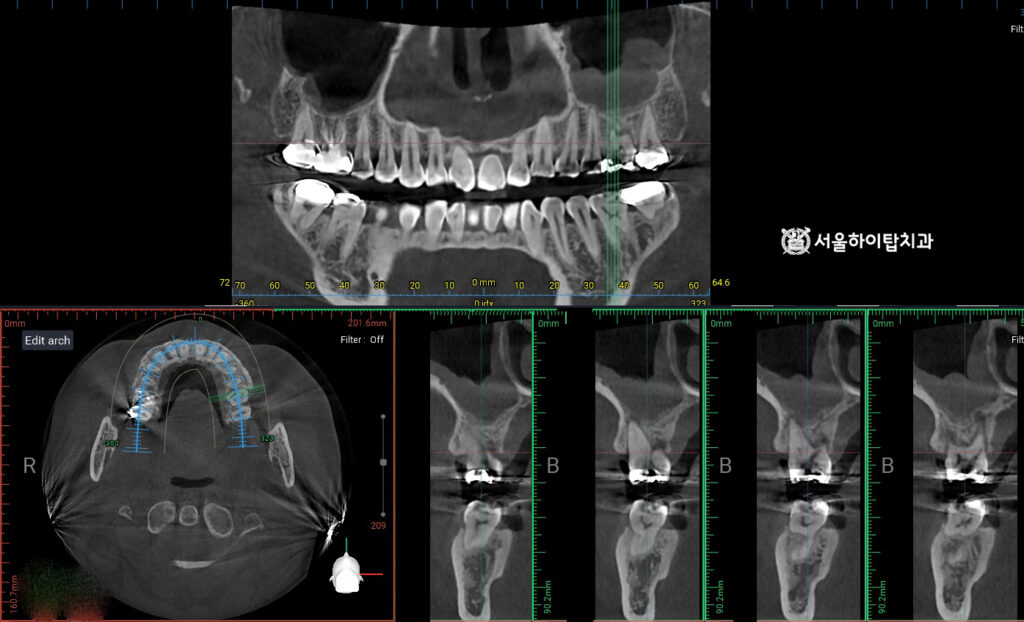

정밀한 CBCT 촬영

만수동 치과 에서는 임플란트가 선택이 되었다면

CT 촬영을 통해 임플란트가 심어질 적절한 위치와

필요한 골량을 먼저 확인하게 된다고 설명해 드립니다.

CT는 치조골의 높이와 두께, 신경과의 거리 등을 3차원으로 평가할 수 있어

안전한 식립을 위한 정확한 수술 계획 수립에 필수적인 과정입니다.

또한 파절로 인해 주변 골 소실이 동반된 경우에는

임플란트 고정에 필요한 골지지가 충분한지 함께 평가하며,

필요 시 골이식 여부나 식립 시점도 이 검사 결과에 따라 결정됩니다.